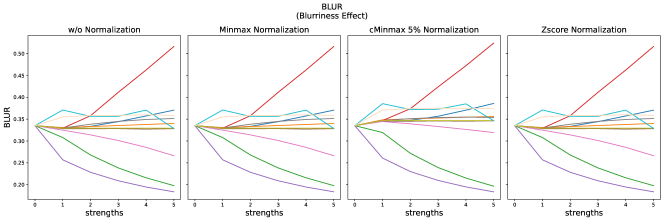

4.2 Non-Reference Metrics

The results for all strengths are given in Fig. A.5. For the maximum strength (s=5), the results are summarized in Tab. 9 without normalization and for cMinMax normalization.

Minmax normalization and Zscore normalization do not have any effect on the selected non-reference metrics, therefore these results are not shown here.

For the BLUR metric, scores clearly increase for blurred images, but also clearly decrease compared to the reference for stripe artifacts, Gaussian noise and the gamma transform for . For small strengths of translation and elastic deformation slightly increased blurriness is measured, but drops again for strengths > 3.